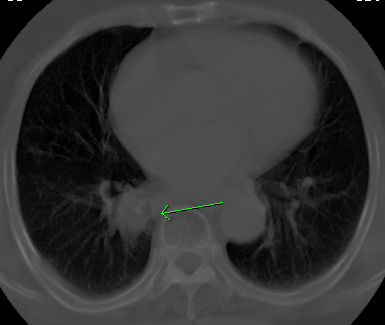

标题: CT26680:肺部右下肺静脉干结节的界定 [打印本页]

标题: CT26680:肺部右下肺静脉干结节的界定

经追查说有支扩咯血病史,但不确定

考虑1、周围型肺癌,2肺静脉畸形,前者可能大,建议增强检查。

不除外淋巴结肿大。

不排除右肺下叶周围型肺癌可能。